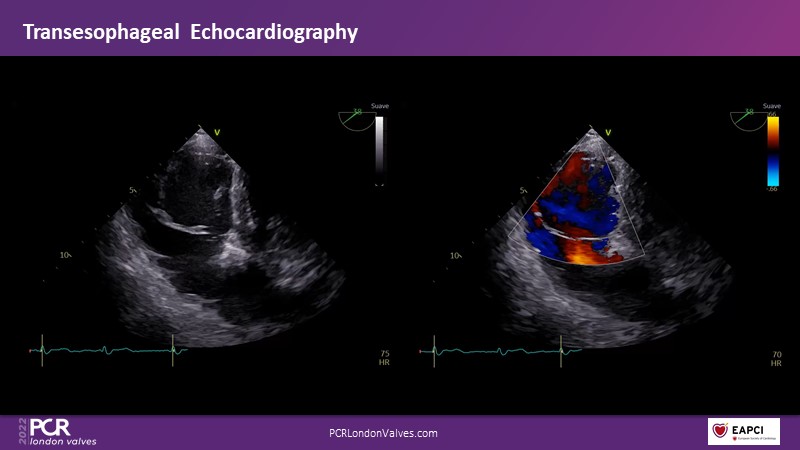

Watch this session if you want to learn tips and tricks that influence procedural strategy through a real-life case as well as anatomical factors that contribute to tricuspid valve complexity and choice of treatment, followed by the latest clinical data.

- To learn more about the anatomical factors that contribute to tricuspid valve complexity and choice of treatment

- To share tips and tricks that influence procedural strategy through a real-life case